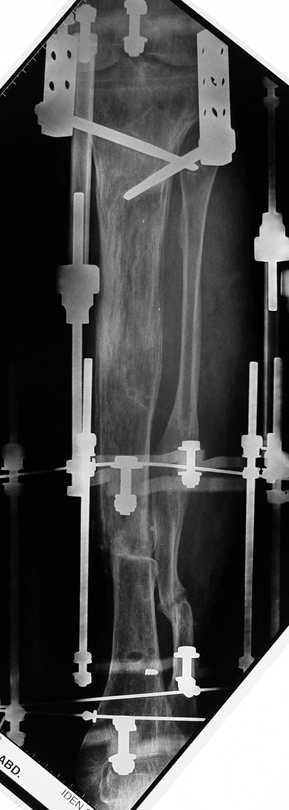

Uygun radikal debridman tüm nekrotik kemik ve yumuşak dokuların çıkartılmasını gerektirir, ve sıklıkla uzuvda instabiliteye neden olur. Kalan kemik ve yumuşak doku defektinin bir şekilde fiksasyonu ve rekonstrüksiyonu gereklidir. İlizarov’un ortaya koyduğu distraksiyon osteogenezi yöntemi, kaynamanın elde edilmesi, deformitenin düzeltilmesi, bacak boy eşitsizliğinin giderilmesi ve segmental defektlerin rekonstrükte edilmesi için başarıyla kullanılmaktadır.

Eksternal fiksatör ile geçen süre (eksternal fiksasyon indeksi), gereken distraksiyon miktarına bağlıdır ve bu süre boyunca bazı komplikasyonlarla karşılaşılabilir. Distraksiyon dönemi sona erdikten sonra, distraksiyon süresinin iki katını aşan konsolidasyon döneminde hastalar eksternal fiksatörü zorlukla tolere edebilirler. Yeterli konsolidasyon sağlanmadan eksternal fiksatör çıkartılırsa ise kırıklar, deformite ve kısalık oluşabilir. Hastanın fiksatör ile birlikte geçirdiği sürenin azaltılması ve böylece hasta konforunun ve aktivite düzeyinin arttırılması için intramedüller çivi üzerinden uzatma yöntemi uygulanmaktadır. Bu yöntemde distraksiyon dönemi sona erdiğinde kemiğin içindeki çivi statik olarak kilitlenmekte ve eksternal fiksatör çıkartılmaktadır. Stabilizasyon intramedüller çivi tarafından sağlandıktan sonra konsolidasyon dönemi gerçekleşmektedir. Bu şekilde hem eksternal fiksatörün uzun süre kalmasından hem de erken çıkartılmasından kaynaklanan komplikasyonların önüne geçilmektedir.